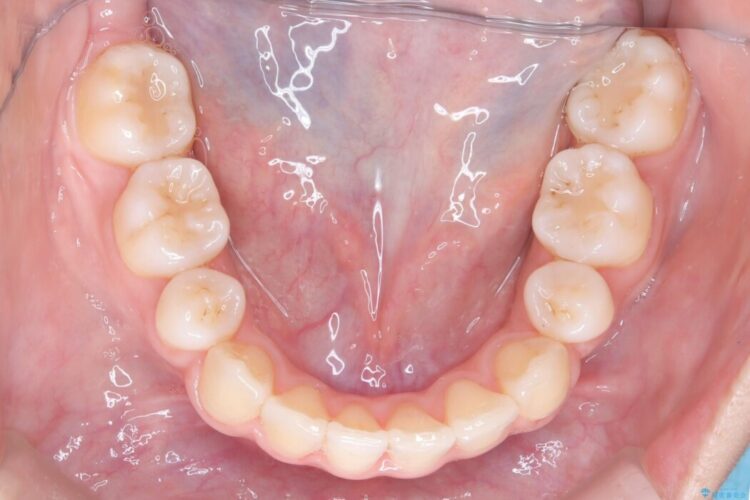

矯正検査の結果、歯を並べるスペースが不足しており、そのまま並べてしまうとさらに突出感が目立つ恐れがありました。

そのため上下左右4番を抜歯し、ガタつきを改善しながら前歯をしっかりと後方へ下げ、口元のボリュームを抑えていく計画を立案しました。

複雑に重なり合っていた前歯を、抜歯で作ったスペースを活用して丁寧に整列。単に並べるだけでなく、角度を1ミリ単位で調整しながら後ろへ下げることで、口元の突出感をスッキリ解消しました。